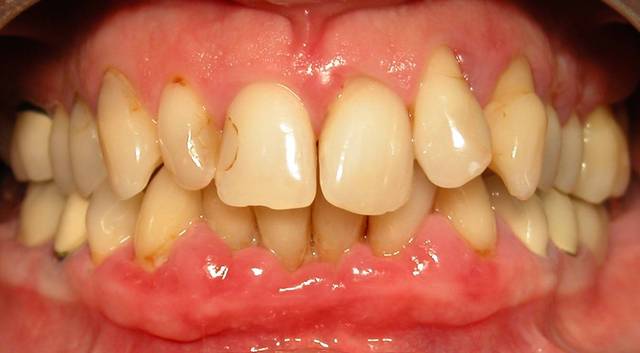

Voici le cas d'une patiente que j'ai traité pour une parodontite chronique.

Donc il s'agite d'une patient adressée par un confrère pour un avis paro avant un traitement ODf. La patiente a cinquante cinq ans. Elle fume des cigares, des problèmes d'hygiène. Je dignostique une parodntite chronique que j'ai traité en non chirurgical. La patiente est en observation avant d'entamer un traitement prothétique plutôt qu'ODF.

La consultation: DSCN 7002

1 mois après la consultation et motivation à l'hygiène: DSCN 7502

Le jour de la lithotriptie: DSCN 7030

6 mois après: DSCN 0013